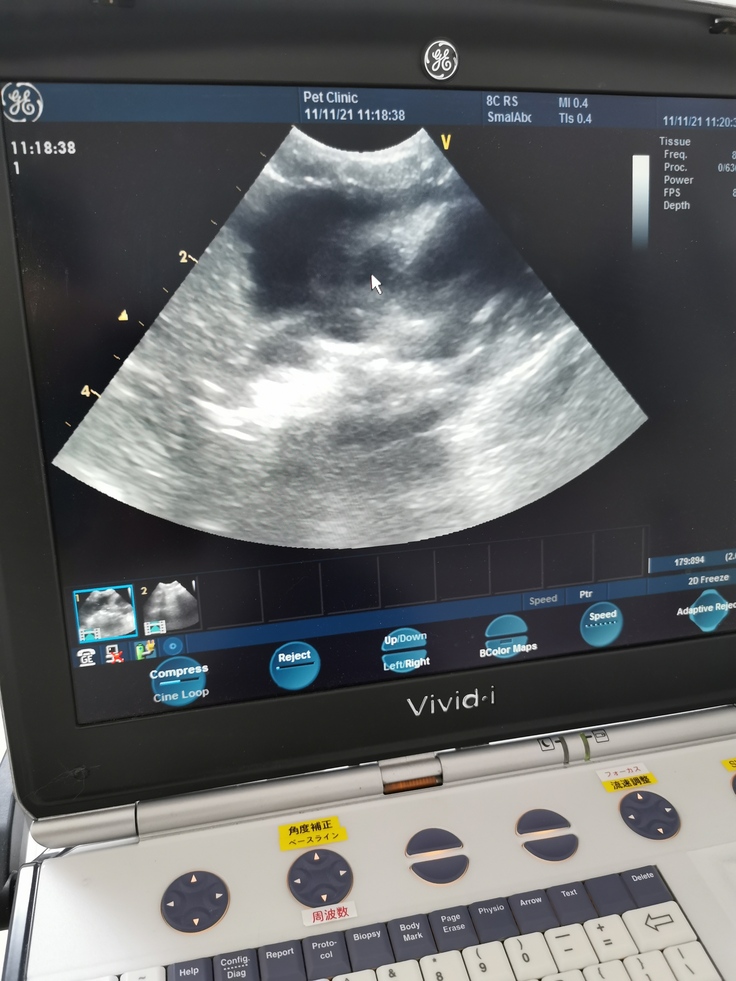

↑胸水を完全には取り除けませんでした。

黒い部分はまだ心臓付近に胸水が残っている部分